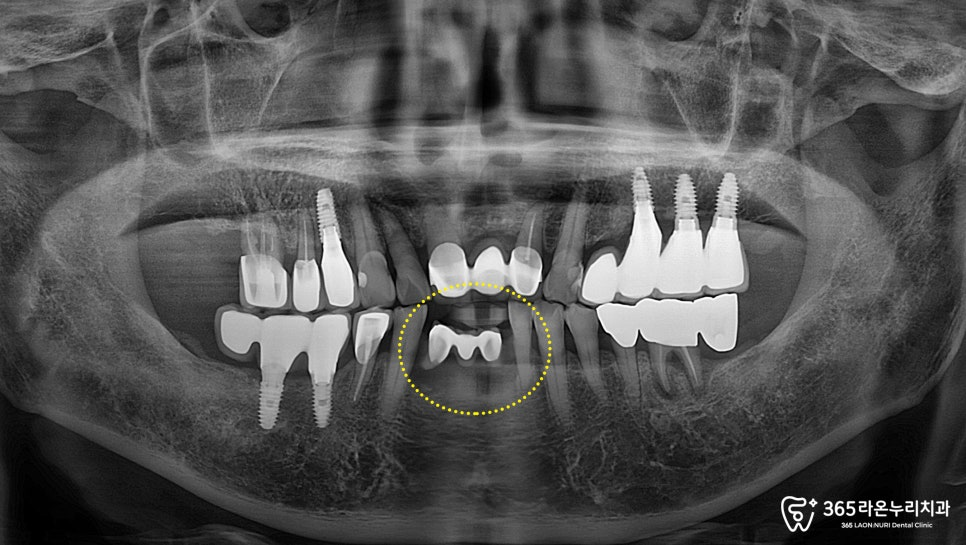

치근단 사진에서도 심한 골흡수 양상이 나타나,

빠른 발치가 필요하다고 판단하게 되었습니다.

그러나 아래 앞니가 없다면

일상 생활 중 많은 불편을 느끼며

다른 부위에도 복합적인 문제가

생길 수 있습니다.

따라서 오산 신장동 치과 에서는

발치 후 즉시 임플란트 식립을

진행하기로 했습니다.